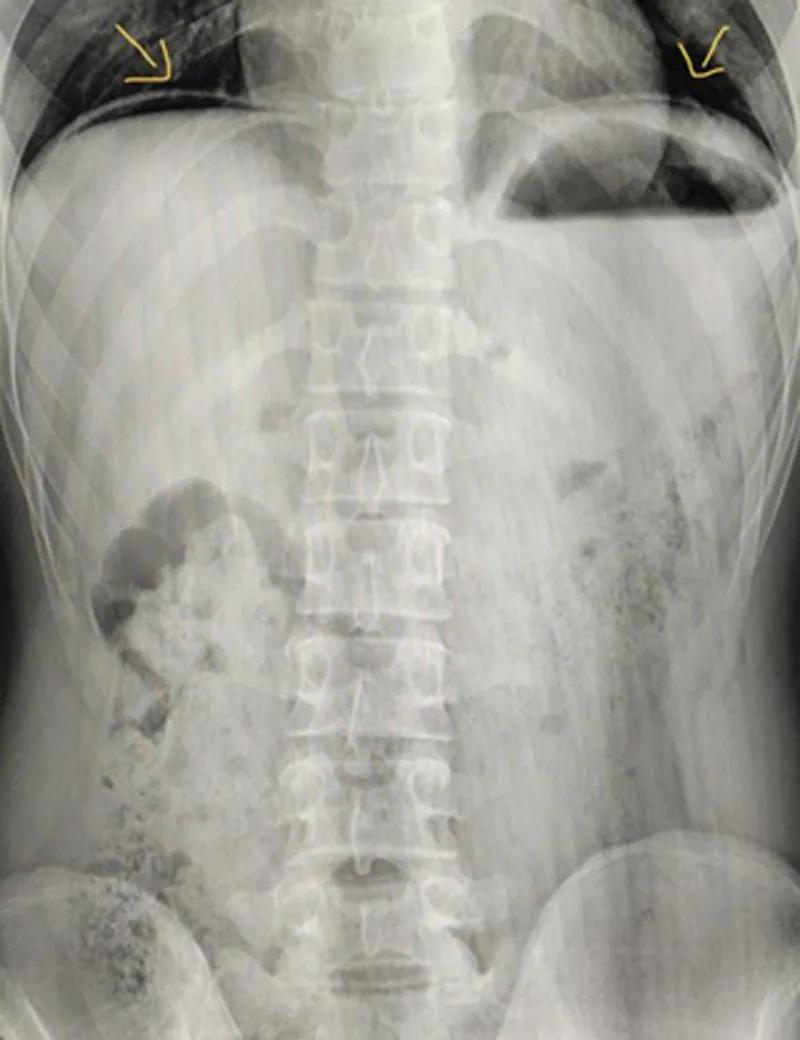

胃肠道穿孔是较常见的急腹症之一。如图为立位腹平片,可以明显看到左右膈肌下都有一条原本不属于那里的透亮弧线(箭头所指),这是膈下游离气体。膈下游离气体出现,说明患者极有可能发生了胃肠道穿孔。